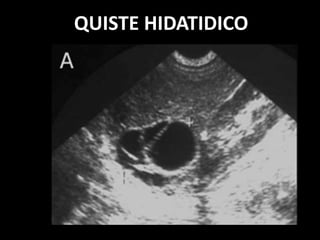

QUISTE HIDATIDICO

LESION BIEN DELIMITADA

PAREDES GRUESAS, CON

CALCIFICACIONES

CONTENIDO INTERNO DENSO.

A VECES UNILOCULADO

FRECUENTE MULTILOCULADO Y CON

VESICULAS HIJAS INTERNAS.

QUISTES HIDATIDICOS SIMPLES

QUISTE HIDATIDICO CON MULTIPLES

QUISTES SATELITES DE MENOR TAMAÑO

QUISTE HIDATIDICO CON VESICULAS

HIJAS INTERNAS